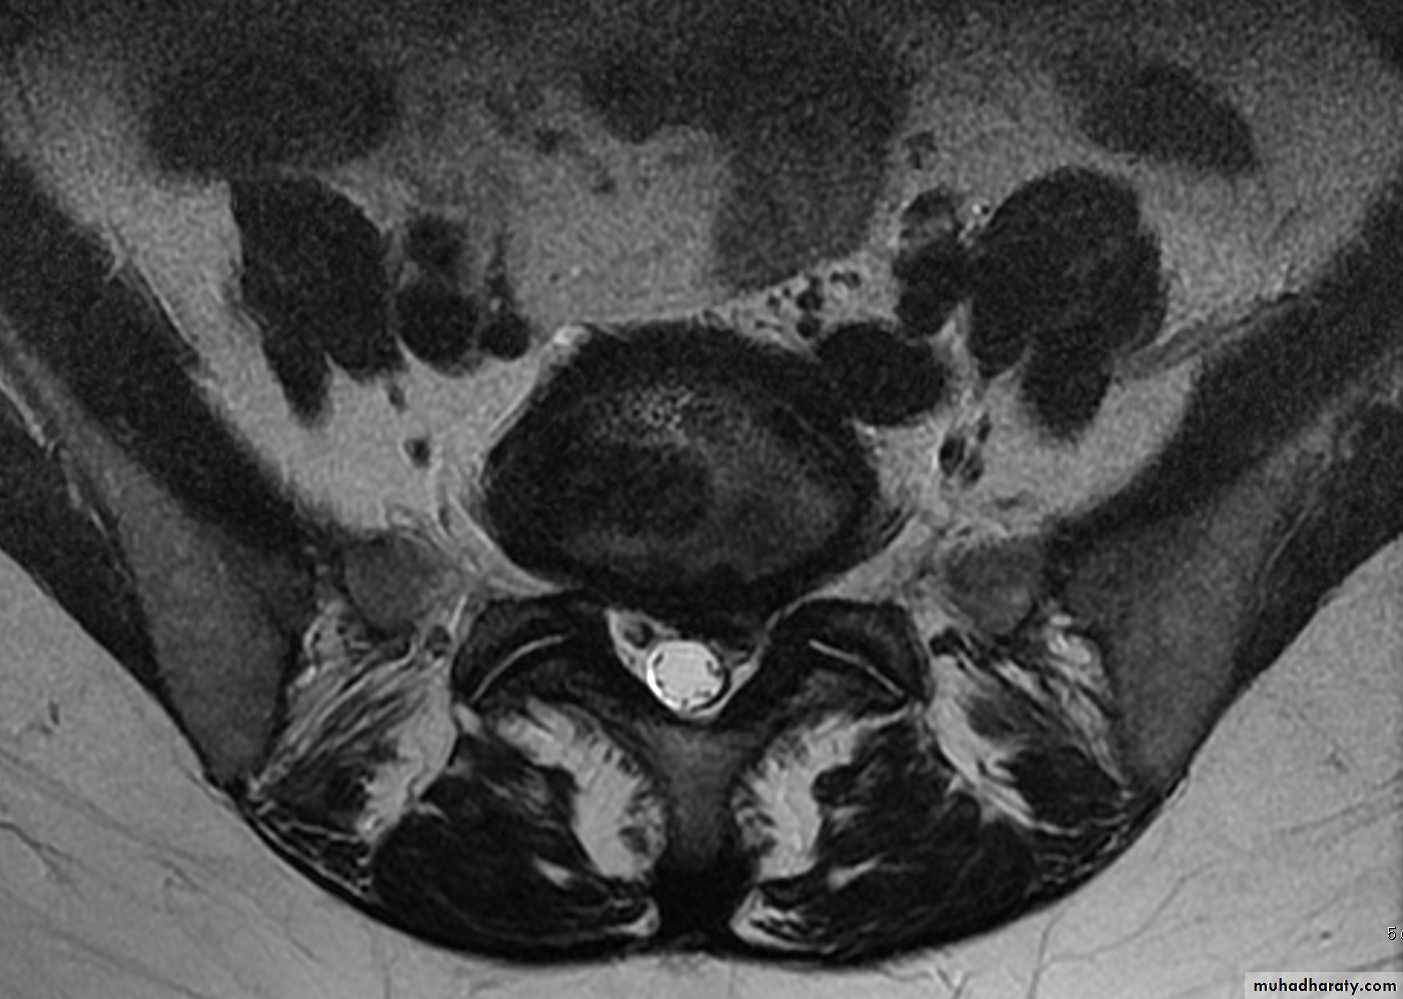

CHRONIC INTERVERTEBRAL DISC DEGENERATIONMRI:

Bulging of the annulus fibrosus in both sagittal and axial projections and diminished thickness and reduced signal intensity (dehydration) of the degenerating disc.

Two measurements are used: the mid-sagittal (anteroposterior) diameter and the inter-pedicular (transverse) diameter of the spinal canal. Normally, the diameters are 15 mm for the anteroposterior and 20 mm for the transverse. Anything less than 11 mm for the anteroposterior diameter and 16 mm for the transverse diameter is considered abnormal.